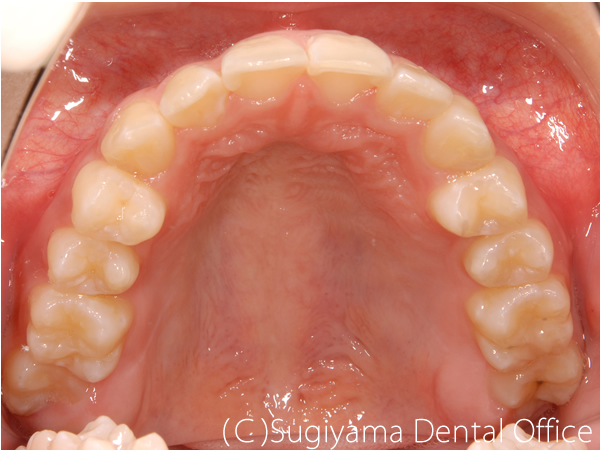

10歳の女性です。 術前写真を見ると、上の前歯2本が内側に傾斜していることがわかります(丸印)。 このような歯の傾斜によって下のあごの位置が奥に押し込まれ顎関節症になる方が少なくありません。

術後1年後には綺麗な歯並びになっただけでなく、機能的なあごの運動ができるようになりました。